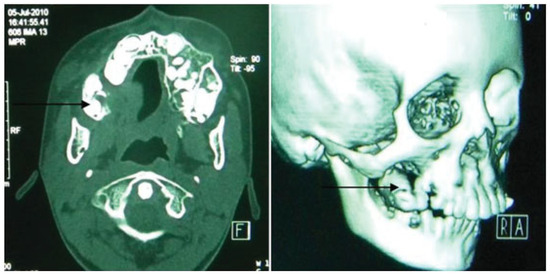

- Incomplete Tessier 7 soft tissue facial cleft and a complete skeletal Tessier 7 cleft on the right side

- Incomplete Tessier 5 skeletal and soft tissue Tessier 6 facial cleft on the left side